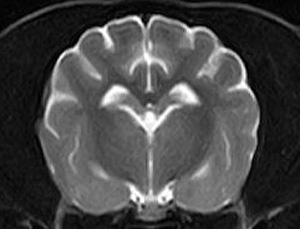

市内の先生からけいれん発作が出るとのことでMRI検査のご依頼がありました。検査では脳に構造上の異常を認めず、脳脊髄液検査も問題なく、特発性てんかんとの診断でご紹介もとの病院様での治療となりました。